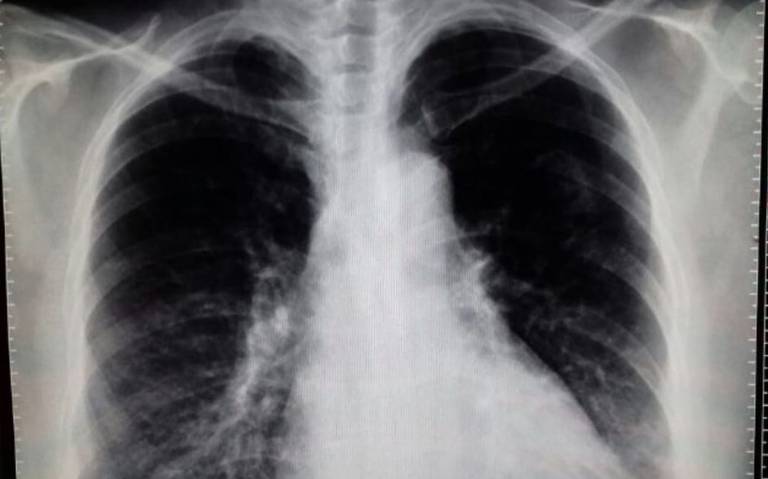

Prevalencia mundial y factores de riesgo de la enfermedad pulmonar obstructiva crónica (EPOC) en 2019

Con más de las tres cuartas partes de los casos globales de EPOC en los países de ingresos bajos y medianos, supone un gran desafío abordar esta afección crónica y creciente para los sistemas de salud en estos entornos. En ausencia de esfuerzos dirigidos a toda la población y reformas del sistema de salud en estos entornos, muchos de los cuales cuentan con recursos insuficientes, podría seguir siendo una tarea difícil lograr una reducción sustancial en la carga de la EPOC a nivel mundial. Lancet Respir Med. 10 de marzo de 2022